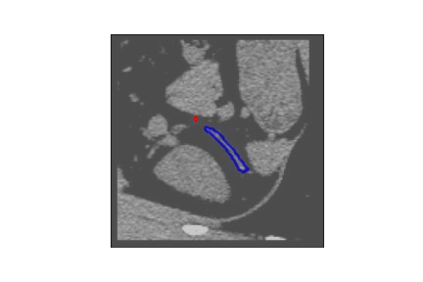

The human annotations are imperfect, especially when produced by junior practitioners. Multi-expert consensus is usually regarded as golden standard, while this annotation protocol is too expensive to implement in many real-world projects. In this study, we propose a method to refine human annotation, named Neural Annotation Refinement (NeAR). It is based on a learnable implicit function, which decodes a latent vector into represented shape. By integrating the appearance as an input of implicit functions, the appearance-aware NeAR fixes the annotation artefacts. Our method is demonstrated on the application of adrenal gland analysis. We first show that the NeAR can repair distorted golden standards on a public adrenal gland segmentation dataset. Besides, we develop a new Adrenal gLand ANalysis (ALAN) dataset with the proposed NeAR, where each case consists of a 3D shape of adrenal gland and its diagnosis label (normal vs. abnormal) assigned by experts. We show that models trained on the shapes repaired by the NeAR can diagnose adrenal glands better than the original ones. The ALAN dataset will be open-source, with 1,594 shapes for adrenal gland diagnosis, which serves as a new benchmark for medical shape analysis. Code and dataset are available at https://github.com/M3DV/NeAR.